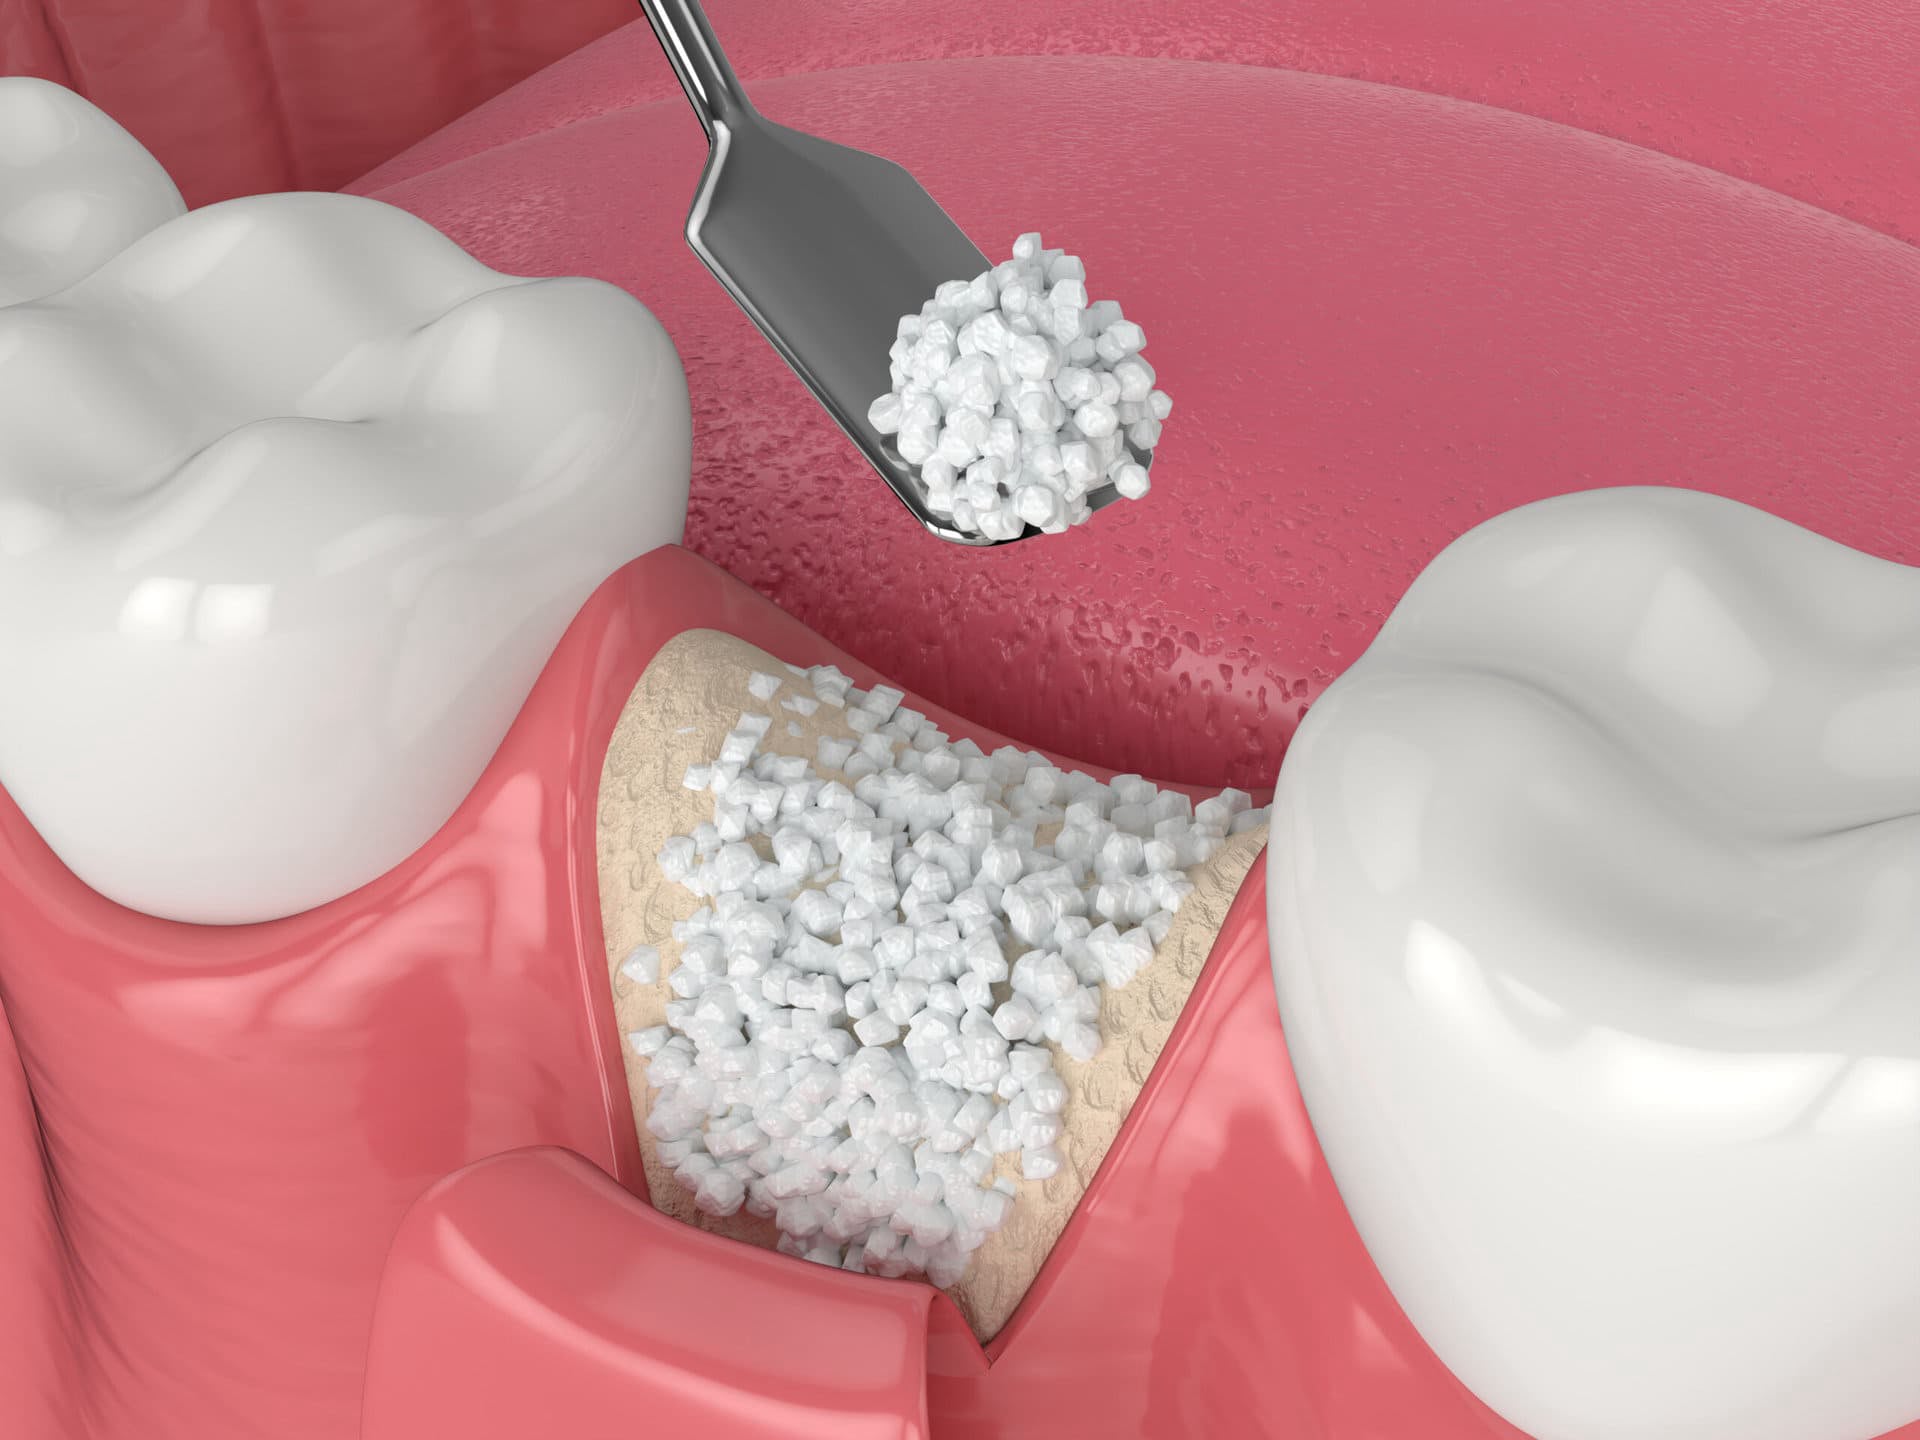

¿Te faltan uno o más dientes?

La pérdida de dientes afecta la estética, la masticación y la salud bucal si no se trata a tiempo.